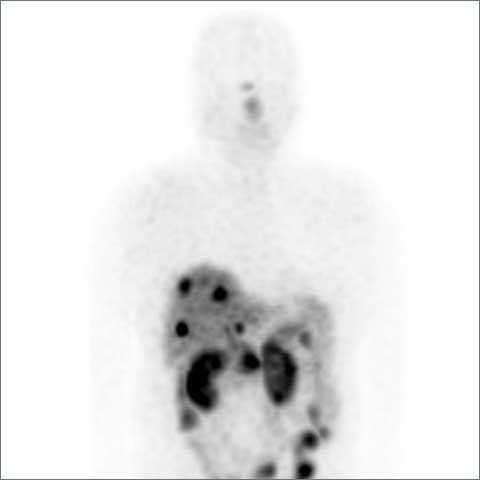

镥-177(Lu177)奥曲肽治疗是一种针对神经内分泌肿瘤患者的靶向放射性核素治疗。该疗法特别适用于在镓-68奥曲肟PET/CT扫描中显示高示踪剂摄取的转移性神经内分泌肿瘤患者。